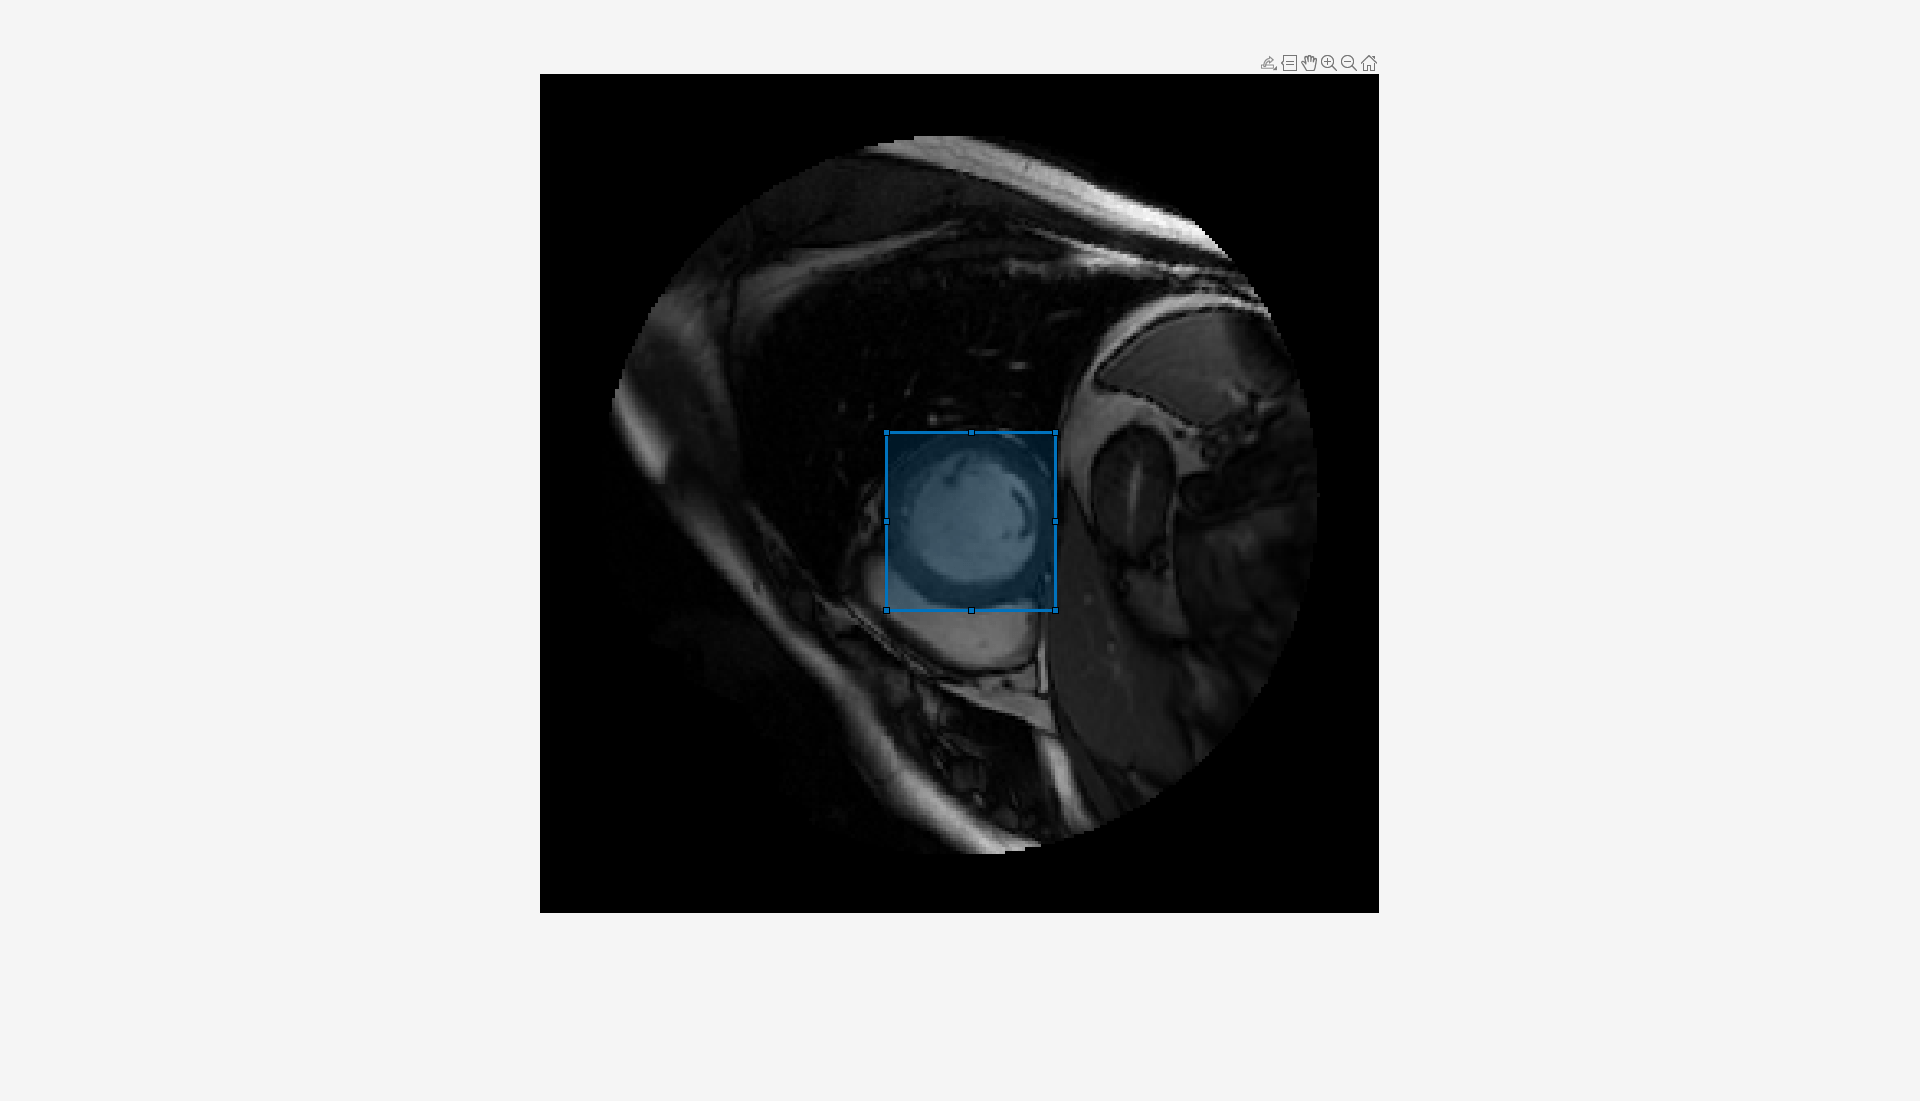

Draw an ROI that contains an object to segment as a Rectangle object on the image by using the drawrectangle function.

roi = drawrectangle(ax);

To segment the object, run the MedSAM decoder on the image embeddings using the segmentObjectsFromEmbeddings object function. Specify the bounding box visual prompt BoundingBox as the position of the rectangle ROI.

mask = segmentObjectsFromEmbeddings(medsam,embeddings,size(img),BoundingBox=roi.Position); overlayedImg = insertObjectMask(rescale(img),mask);

Visualize the segmentation mask overlaid on the image in the image display.

dispIm.CData = overlayedImg;

Analyze the segmented object using the analyzeObject helper function provided at the end of this example. The analyzeObject helper function performs radiomics analysis in the region indicated by the segmentation mask returned by the MedSAM decoder, and extracts key features such as surface area, major axis length, minor axis length, mean intensity, and intensity variance of the segmented region. The function then displays these key radiomics features as text near the segmented region in the image.